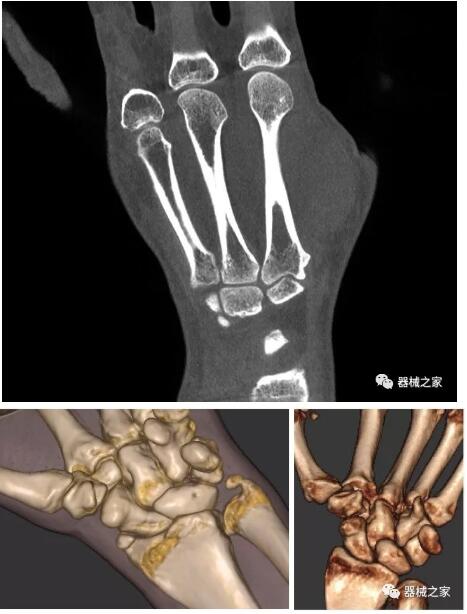

以上介紹的CT均來自國外同一家公司,這些CT均配置了可視化軟件,可以進行切片、3D重建以及大型CT附帶的所有典型的操作功能。

以下是這些“特立獨行”的CT所拍出來的圖像: